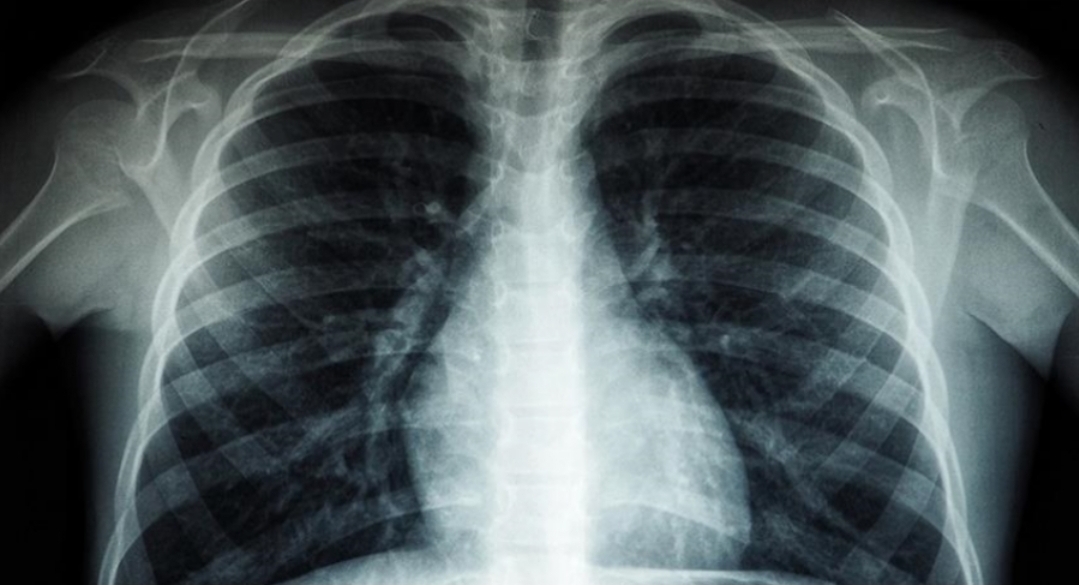

Drejtori Rajonal i Organizatës Botërore të Shëndetësisë (OBSH) për Evropën, Hans Kluge, njoftoi se 1 milion njerëz vdesin çdo vit nga tuberkulozi, “sëmundja infektive më vdekjeprurëse në botë”

“Tuberkulozi është sëmundja infektive më vdekjeprurëse në botë, duke vrarë 1 milion njerëz çdo vit”, tha Kluge.

Ai ka shtuar se rezistenca ndaj ilaçeve, bashkë-infeksioni tuberkuloz-HIV, qasja e pabarabartë në kujdesin shëndetësor dhe financimi i pamjaftueshëm po e përkeqësojnë më tej krizën.

Në “Raportin Global të Tuberkulozit 2025”, të botuar më 12 nëntor, OBSH-ja raportoi se më shumë se 1.2 milionë njerëz kanë humbur jetën nga tuberkulozi në vitin 2024, dhe afërsisht 10.7 milionë njerëz u prekën nga sëmundja.